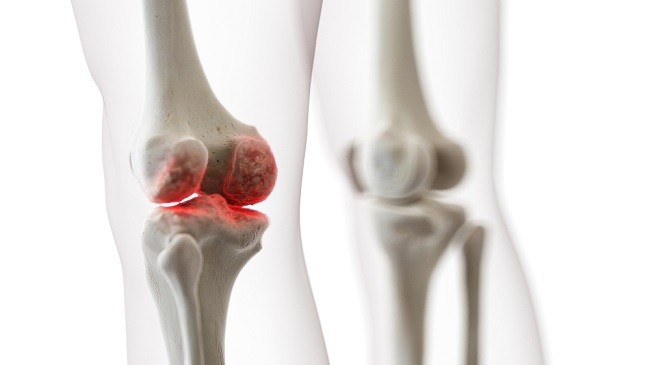

Đau nhức đầu gối có thể gây biến dạng khớp

Biến dạng khớp: Đầu gối sưng viêm có thể gây biến dạng lệch một bên hoặc lõm vào gây đau đớn.